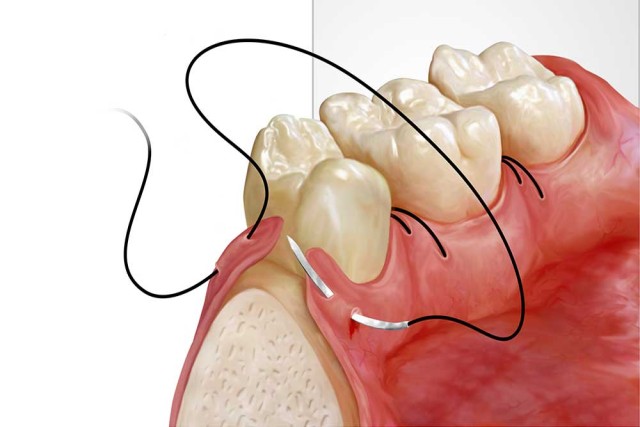

Wisdom tooth removal

Surgical extraction of impacted or problematic wisdom teeth.

Suturing of facial lacerations

Repair and healing of facial cuts or injuries.